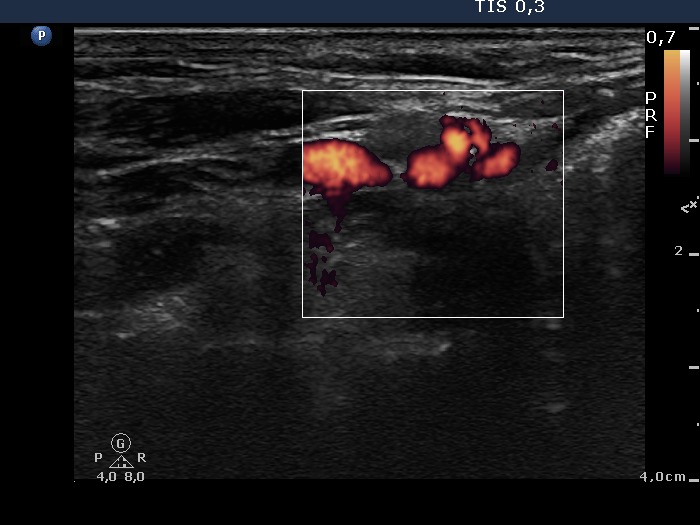

100 consecutive cases of papillary cancer - case 022 (ultrasonographic picture 10)

Right side of the neck, color Doppler mode. One of the hypoechogenic lesions is not a vessel but a lymph node. This was also aspirated and proved to be a metastatic papillary cancer.